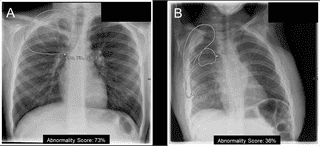

Trí tuệ nhân tạo (AI) đang thay đổi nền y tế, nhưng chỉ khi được phát triển có trách nhiệm – minh bạch, an toàn, và đặt con người ở trung tâm – mới thật sự mang lại lợi ích bền vững cho cộng đồng.

Với sự phát triển mạnh mẽ của công nghệ, ứng dụng trí tuệ nhân tạo (AI) trong lĩnh vực chăm sóc sức khỏe đã trở nên vô cùng phổ biến và mang lại nhiều lợi ích đáng kể. Tuy nhiên, việc sử dụng các công nghệ này cũng đặt ra nhiều rủi ro và thách thức.